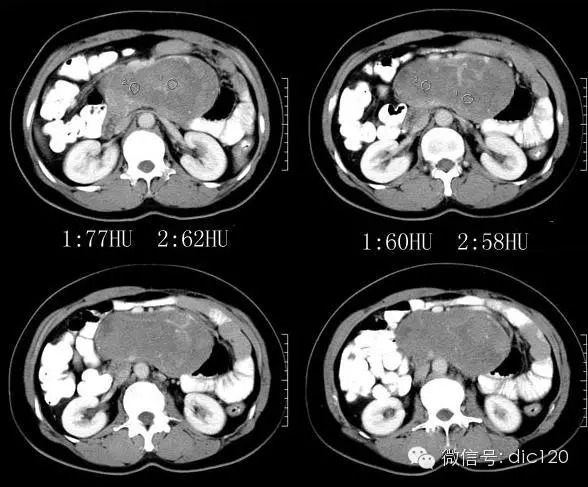

【病史临床】患者,女性,51岁。体检B超发现左中腹巨大肿块。

平扫:腹膜后区域可见形态略不规则的类椭圆形肿块影,密度比较均匀;边缘大部分清晰,与主动脉和部分肠壁的边缘模糊,且脂肪间隙消失;周边脂肪的密度比较均匀;肠系膜上动脉,肠系膜上静脉,肠系膜及肠管向前方和侧方受压移位明显;腹腔内未见明显的肿大淋巴结。增强:动脉期肿块强化并非明显,但可见增多、增粗、迂曲的供血血管影;静脉期肿块强化的略明显,且略有不均匀,可见形态不规则的低密度轻微强化或者不强化的区域。

1.肿块巨大与腹部大血管关系密切.局部肠腔向前外侧推移改变.跨中线向两侧生长;

2.肿块密度相对均匀质,界清,与胰腺分界清晰;

3.增强渐进明显强化,内部示粗大较规则血管影;定位:后腹膜;定性:低度恶性间叶组织来源肿瘤>神经源性肿瘤。

手术所见:腹壁可见约12cm长手术疤痕。回肠部分与腹壁粘连,可见腹膜后肿瘤约15x16cm,不规则,有完整包膜,质软,将肠系膜、血管顶起,血管明显增粗,瘤体血管丰富,压迫腹主动脉,与胰尾粘连。行“腹膜后肿瘤切除术”。

病理诊断:恶性间叶组织肿瘤。